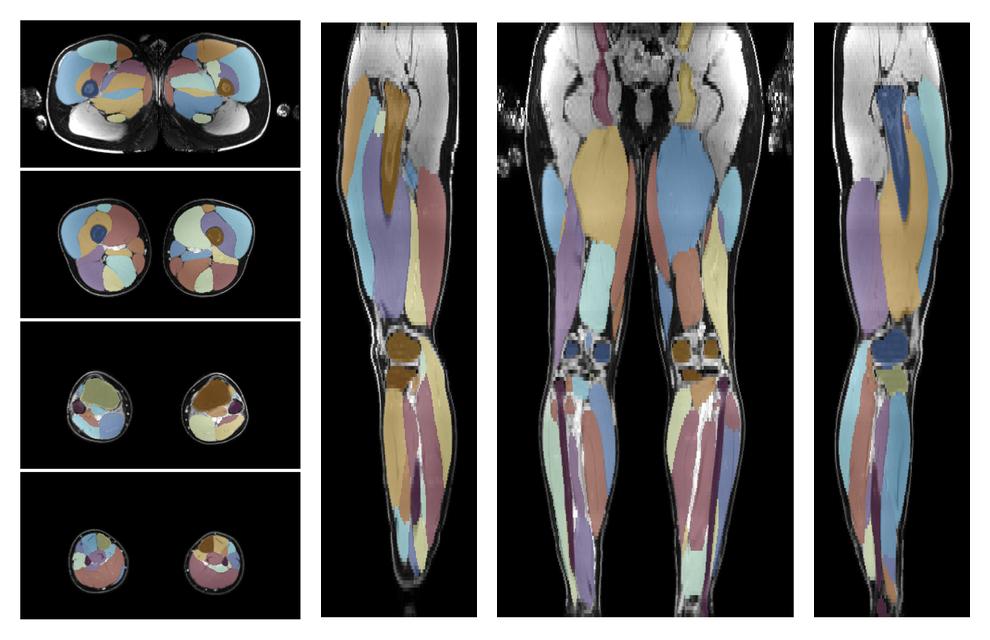

• Automated muscle and bone segmentation.

Overlay of automated muscle segmentation labels on dixon water image.